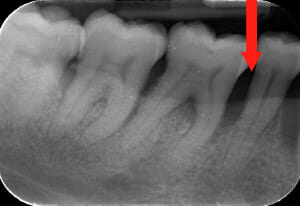

Endorale prima e dopo la cura della parodontite

Con terapia parodontale fotodinamica non chirurgica: si noti la ricrescita naturale dell’osso e del tessuto parodontale.